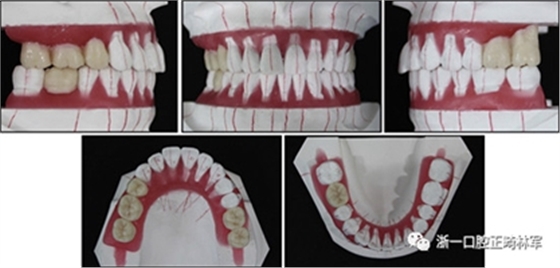

完成診斷性設計后,治療后穩(wěn)定的咬合是確定的(圖5)。進行治療之前,治療計劃和順序需要通過涉及正畸,牙周病和修復的多學科綜合治療方法加以確認(圖6)。牙周治療應在正畸治療前完成。牙周疾病的治療采用全口潔治,上頜和下頜前牙區(qū)的刮治術,以及下頜左側后牙區(qū)的翻瓣手術。休息3個月后,幾乎每個部位都實現(xiàn)了牙周袋深度縮小,探針出血幾乎沒有(表III)??刂蒲装Y后,開始正畸治療。在正畸治療期間定期進行牙周維護的復診檢查。

圖5. 治療計劃的診斷性設置

圖6. 治療計劃和應用正畸學,牙周學和修復學的跨學科綜合治療順序